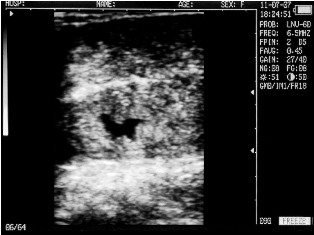

Uterine horn heifers